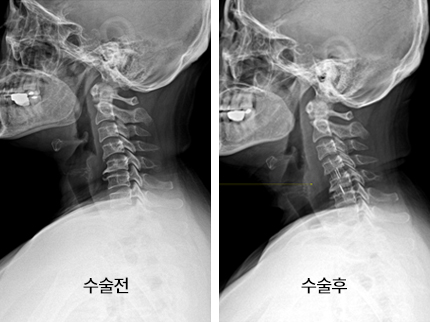

척수라는 중추 신경은 목뼈를 통과해 목 아래 감각과 운동 신경에 영향을 끼치기 때문에 목 디스크 증상들이 나타나면 신속하고 빠른 대처가 필요해요. 목디스크 치료형식으로 주로 초기 스탭에는 물리치료나 약물을 통해 대개의 환자들이 호전돼요. 그렇지 않다고 하면 신경 성형술과 차단술이라고 부르는 뼈주사 목디스크 치료방법을 이용하는데, 이 치료방법은 통증이 있는 신경 부위에 약물을 삽입하는 것입니다.

시술로써 눈에 띄게 질환을 현저히 치료하시는 것이 아니라 염증을 보완하고 통증을 낮추는 것이 포인트입니다. 이러한 방식으로 비 수술적인 치료를 3개월 이상 넘었음에도 불구하며 증상이 호전을 보이지 않으신다면 목디스크 치료방법 중 수술적 치료를 고심해야 하더라고요. 인공디스크를 투입하기 위함으로 절개를 통하기에 디스크를 제거하며 뼈를 하나로 유합 시켜서하는 것과, 내시경 수술로 빠져 나온 수핵 자체만을 제거시켜서하는 방법이 있다고하고요.

목디스크 수술

수술 방법에도 많은가 있다고 하는데 개괄적으로 설명을 하면 목을 절개해 망가진 디스크를 제거한 뒤 뼈를 하나로 유합하는 방법, 인공 디스크 투입술, 내시경을 활용해 바깥으로 빠져나온 수핵을 없애는 수술법 등이 있다고 합니다.